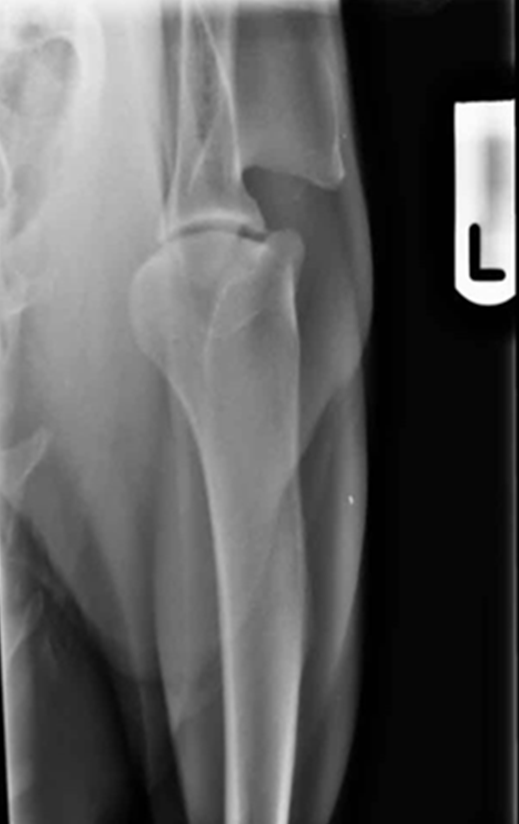

What should be seen in a well positioned caudo-cranial view of a shoulder radiograph?

§A well positioned radiograph has the scapula and humerus in line with each other

§Centering on the middle of the joint means there is good visualisation of the joint space

label

scapula

spine of scapula

acromion process

greater tubercle

intertubercle groove

coracoid process

lesser tubercle

supraglenoid process

glenoid cavity

humerus